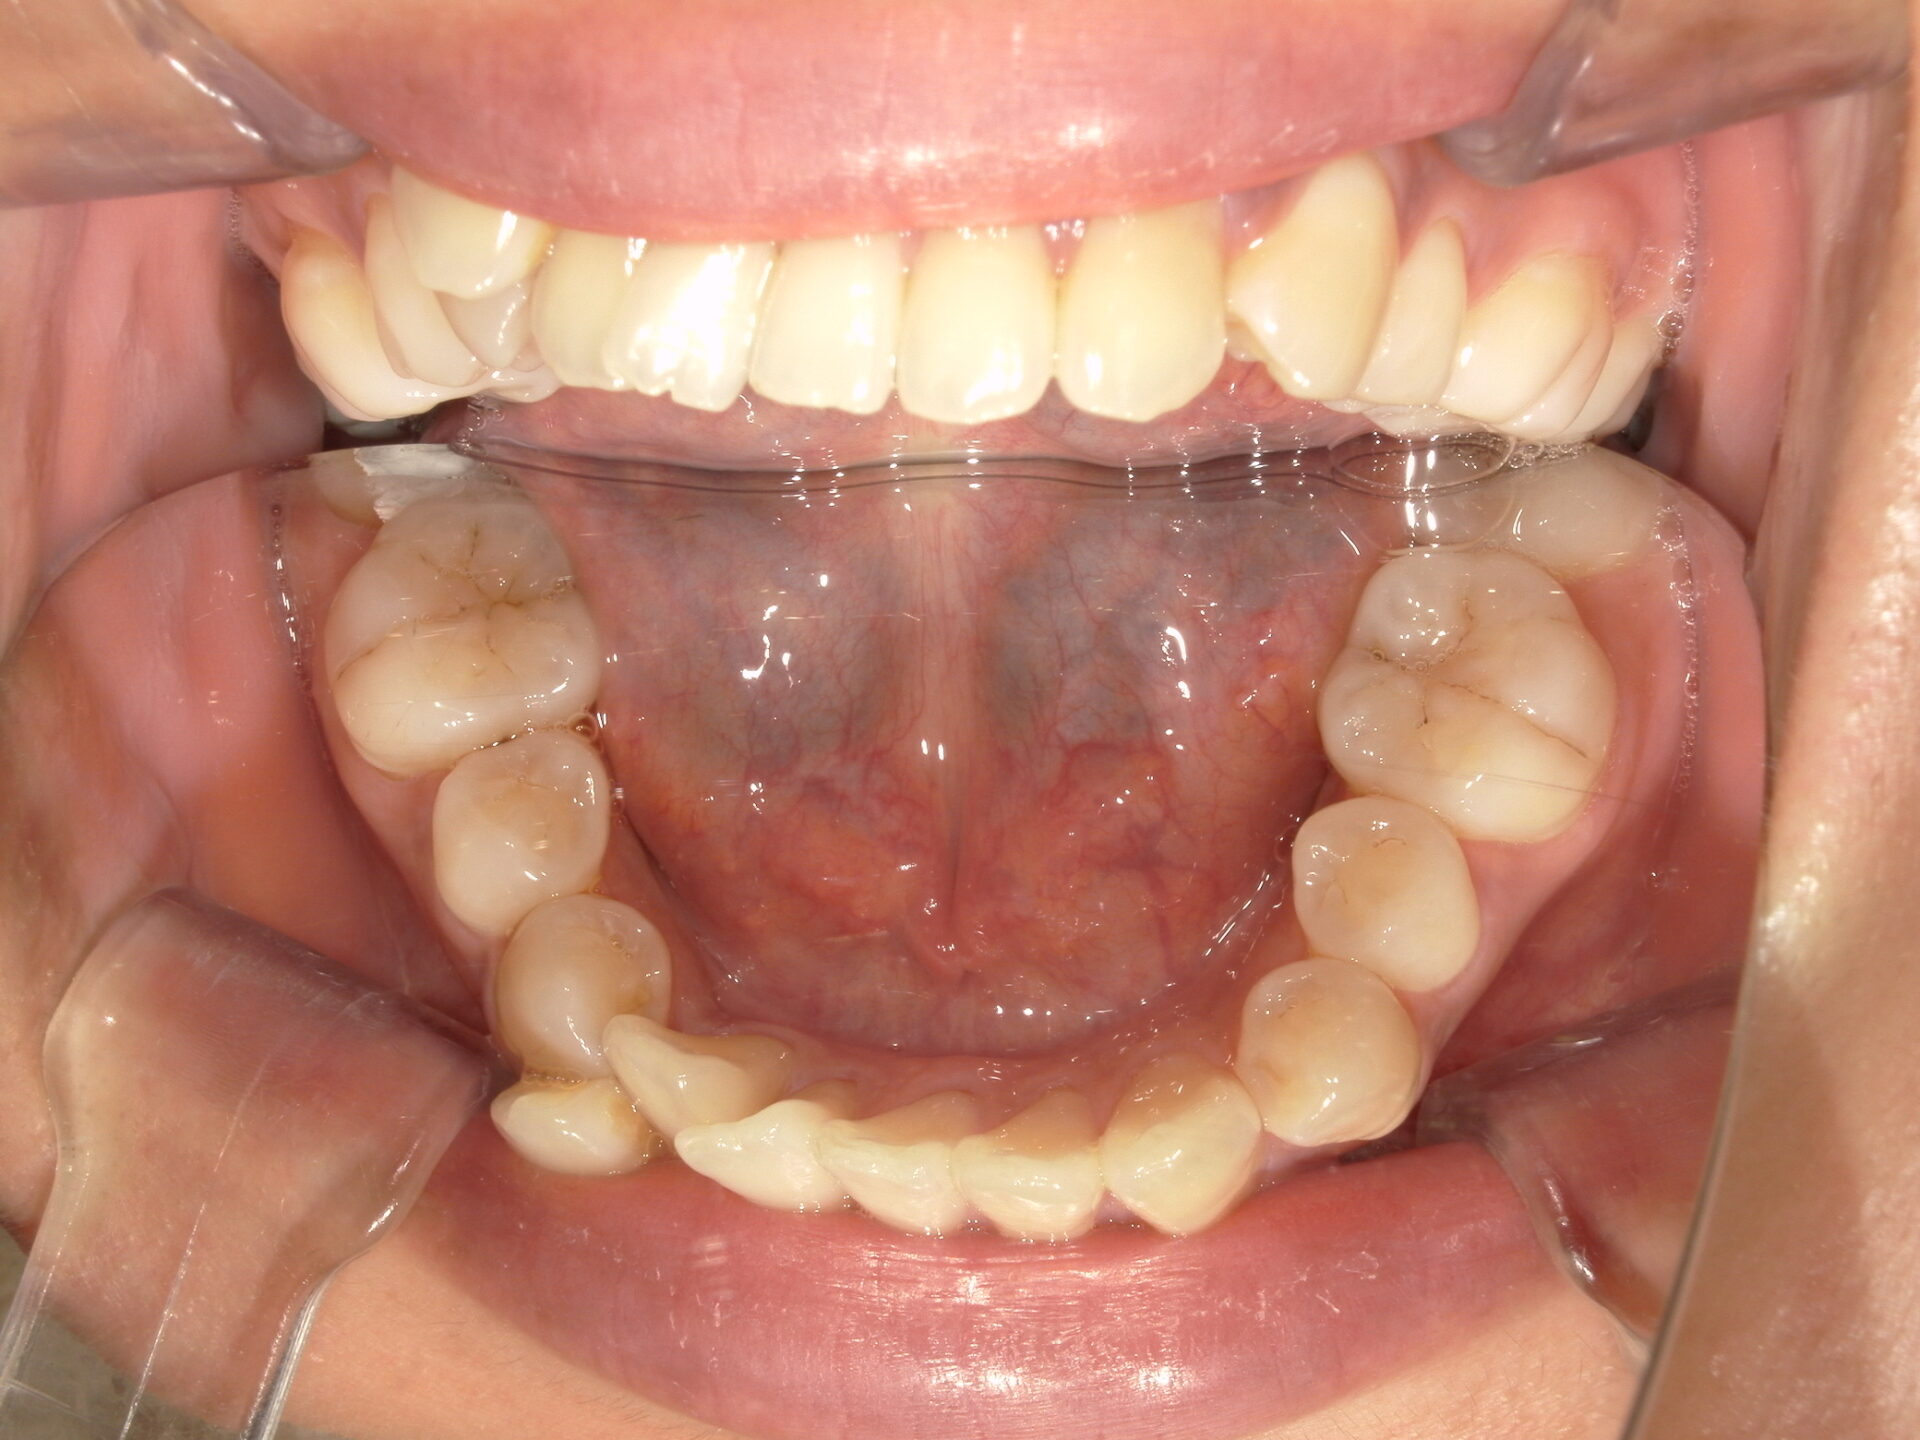

before

患者さんの年齢 20代 女性 症状 見た目が良くなりたい 治療内容 マウスピース矯正治療 費用 90万(税抜) 治療期間・回数 治療期間2年半、通院回数20回 メリット スマイルラインが綺麗 デメリット・リスク 期間がかかることがある 患者さまの声 見た目が綺麗になった - マウスピース矯正